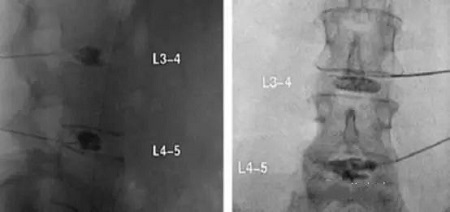

X線矢狀位和前后位L3-4和L4-5椎間盤造影術